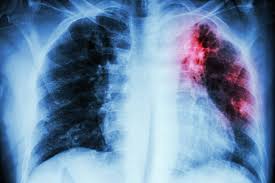

Book your appointment now with Dr. Ria Shah who is known as the Best Lung Fibrosis Specialist in South Mumbai. Scarring (fibrosis) of the lung tissue is a hallmark of lung fibrosis, sometimes referred to as pulmonary fibrosis, a chronic and progressive lung disease. It becomes harder to breathe and for oxygen to enter the bloodstream as a result of this scarring because it thickens and stiffens the lungs. Autoimmune conditions (such as rheumatoid arthritis), prolonged exposure to environmental contaminants, certain drugs, radiation therapy, and, frequently, unidentified causes (idiopathic pulmonary fibrosis or IPF) are common causes. Typical symptoms for patients include exhaustion, shortness of breath, a chronic dry cough, and decreased tolerance to physical activity. Respiratory failure may result from lung fibrosis if treatment is delayed. Specialists in identifying and treating lung fibrosis, pulmonologists are essential in reducing the course of the illness and enhancing quality of life.

a) Accurate Diagnosis: Pulmonologists use high-resolution CT scans, pulmonary function tests (PFTs), and sometimes lung biopsies to confirm the diagnosis and identify the type of fibrosis.